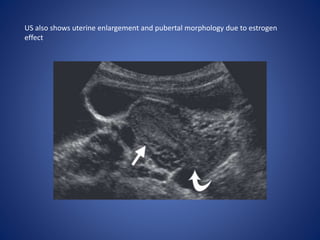

As an ovarian tumor, juvenile GCT is usually initially identified at US, with

demonstration of a large mixed cystic and solid mass.

US also shows uterine enlargement and pubertal morphology due to estrogen

effect

Juvenile GCT ofthe Ovary Juvenile GCT is a malignant primary ovarian neoplasm of children and young adults that is most often characterized by clinical manifestations of steroid hormone overproduction. The lesion is classified as a sex cord–stromal tumor. Imaging Features.— As an ovarian tumor, juvenile GCT is usually initially identified at US, with demonstration of a large mixed cystic and solid mass.

• 61.

US also showsuterine enlargement and pubertal morphology due to estrogen effect